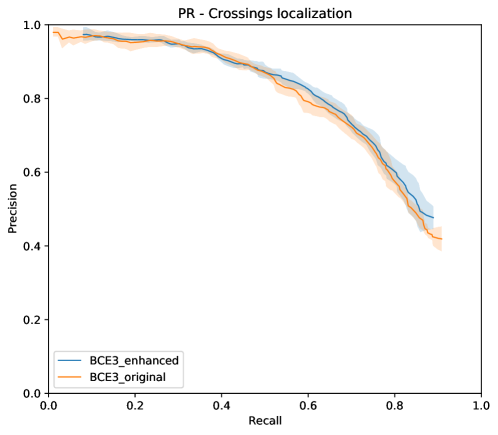

Figure 11 depicts the PR curve for vessel crossing localization in RITE-test set for the networks trained using the MS approach.

In addition to the higher segmentation performance using BCE3, crossings are handled in a more intuitive way. In this case, crossing pixels are simply assigned to both artery and vein classes at a time and the network is able to detect them (see PR curve depicted in Figure 11) while allowing to achieve a continuous segmentation of both the arterial and venular trees. For CE4, differently, the crossings are mostly treated as a separate class (along with the uncertain vessels), either to detect them [39], or to let the network detect the artery or the vein above the other [36, 37, 40, 41]. There is also some approach in which the crossings belong to the same class as that of the upper vessel [38]. Nevertheless, whichever of these alternatives gives raise to incomplete segmentation maps for both arteries and veins. Multiple examples of this effect can be found in Figure 14. Taking all this into account, it can be stated that the MS strategy favors a better segmentation of the different structures, and handles the different cases in a much simpler way.

Finally, it should be noticed that the proposed method presents an additional advantage over the rest of the state-of-the-art approaches: it allows to detect vessel crossings with a satisfactory performance. This aspect is distinctive of our work, since there is no other in the state of the art that allows to perform this task. Additionally, our approach gives raise to fully-connected arterial and venular trees. This factor facilitates the structural analysis of both types of vessels, and it is useful for the future application of methods for addressing the vascular coherence issue. Furthermore, it remarkable that these advantages are achieved with a simple change in the loss; a change that also simplifies the approach of the problem and significantly improves the performance on the vascular segmentation task.